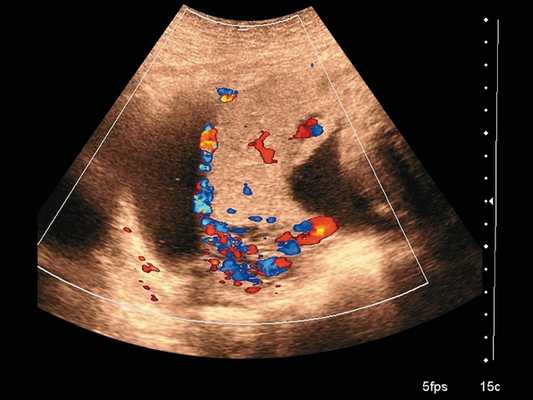

Рис. 1. Беременность 28 +6 нед. Ретроплацентарные лакуны, отсутствие нормальной гипоэхогенной ретроплацентарной зоны, истончение миометрия, гиперваскуляризация пузырно-маточной зоны. Режим ЦДК.

Рис. 3. Беременность 28 +6 нед. Васкулярная инвазия в шейку матки. Режим ЦДК.

Сканирование в сроке 32 +4 нед беременности проводилось на ультразвуковом сканере премиум-класса W10 (компании Samsung) c использованием конвексного (CA1-7A) и внутриполостного (EV3-10B) датчиков с применением технологии LumiFlow™ (рис. 4-7).

Рис. 4. Беременность 32 +4 нед. Ретроплацентарные лакуны, отсутствие нормальной гипоэхогенной ретроплацентарной зоны, истончение миометрия, выпячивание плаценты.

Рис. 5. Беременность 32 +4 нед. Ретроплацентарные лакуны, отсутствие нормальной гипоэхогенной ретроплацентарной зоны, истончение миометрия, гиперваскуляризация пузырно-маточной зоны. Режим ЦДК.

В режиме серошкального сканирования все ранее идентифицированные особенности плацентации (PAS 3a): ретроплацентарные лакуны, васкулярная инвазия в шейку матки, исчезновение нормальной гипоэхогенной ретроплацентарной зоны, истончение миометрия, выпячивание плаценты, гиперваскуляризация пузырно-маточной зоны были подтверждены.

Дополнительное использование технологии стереоскопической визуализации кровотока (LumiFlow™) позволило визуализировать вовлеченность стенки мочевого пузыря беременной в конгломерат тканей аномальной плацентации (сосудистые мостики (rail sign) из миометрия сквозь серозный покров в стенку мочевого пузыря), то есть идентифицировать placenta percreta (PAS 3b). Проведенная в последующем МРТ констатировала полное предлежание плаценты с прорастанием в рубец, через все слои миометрия, шейку матки и цервикальный канал (рис. 8) и верхнюю стенку мочевого пузыря.